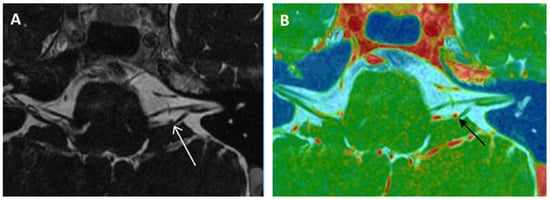

- Kierig, E.; Gerb, J.; Boegle, R.; Ertl-Wagner, B.; Dieterich, M.; Kirsch, V. Vestibular paroxysmia entails vestibular nerve function, microstructure and endolymphatic space changes linked to root-entry zone neurovascular compression. J. Neurol. 2023, 270, 82–100. [Google Scholar] [CrossRef] [PubMed]